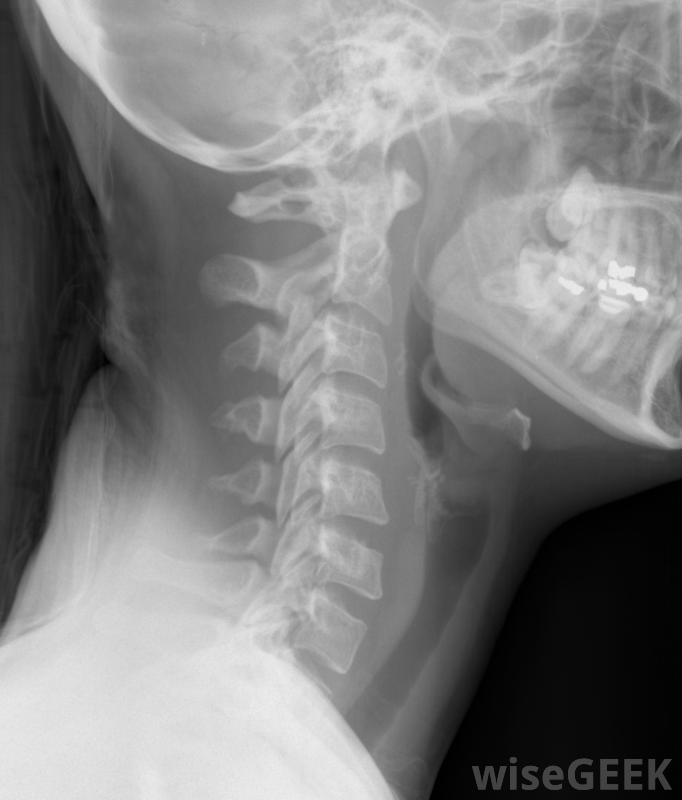

颈部的X光片,包括颈椎。并不是所有的颈部弥漫性隆起都会出现症状。但是,由于颈部隆起会压迫脊椎的神经,可能会出现各种症状。症状可能包括颈部疼痛,这种疼痛会辐射到肩部,手臂和手。人的手也可能有刺痛感或麻木感。